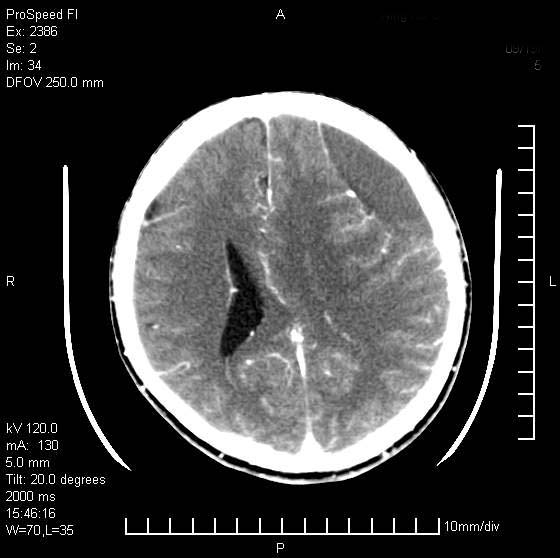

以下是引用天南地北在2007-9-19 18:43:00的发言:[br]典型慢性硬膜外血肿[br][br][本贴已被 天南地北 于 2007-9-19 18:44:11 修改过]

以下是引用曼一拍在2007-9-20 11:06:00的发言:[br]支持慢性硬膜下血肿.[br]慢性硬膜下积液:血肿有包膜,ct值稍高于脑脊液,增强可有染色。不典型者血肿可多呈梭形.是硬脑膜与蛛网膜之间的潜在腔隙内的血肿。[br]鉴别:[br]1\\硬膜外血肿:是颅脑外伤后脑膜或板障内血管破裂,血液在颅骨与硬膜之间积聚所致.通常是脑膜动脉破裂,也可因静脉窦破裂或颅骨的板障静脉出血,发生于外伤的着力部,常与颅骨骨折并存。脑膜动脉出血则急,若是板障静脉出血在则可有慢性。[br]2\\硬膜下积液:(硬膜下水瘤)[br]是由于蛛网膜破裂,脑脊液经蛛网膜破口进入硬膜下腔不能回流。或水肿阻塞而形成。[br]ct表现:颅骨内板下方新月形低密度区近似脑脊液密度;占位效应清,周围无脑水肿。[br]